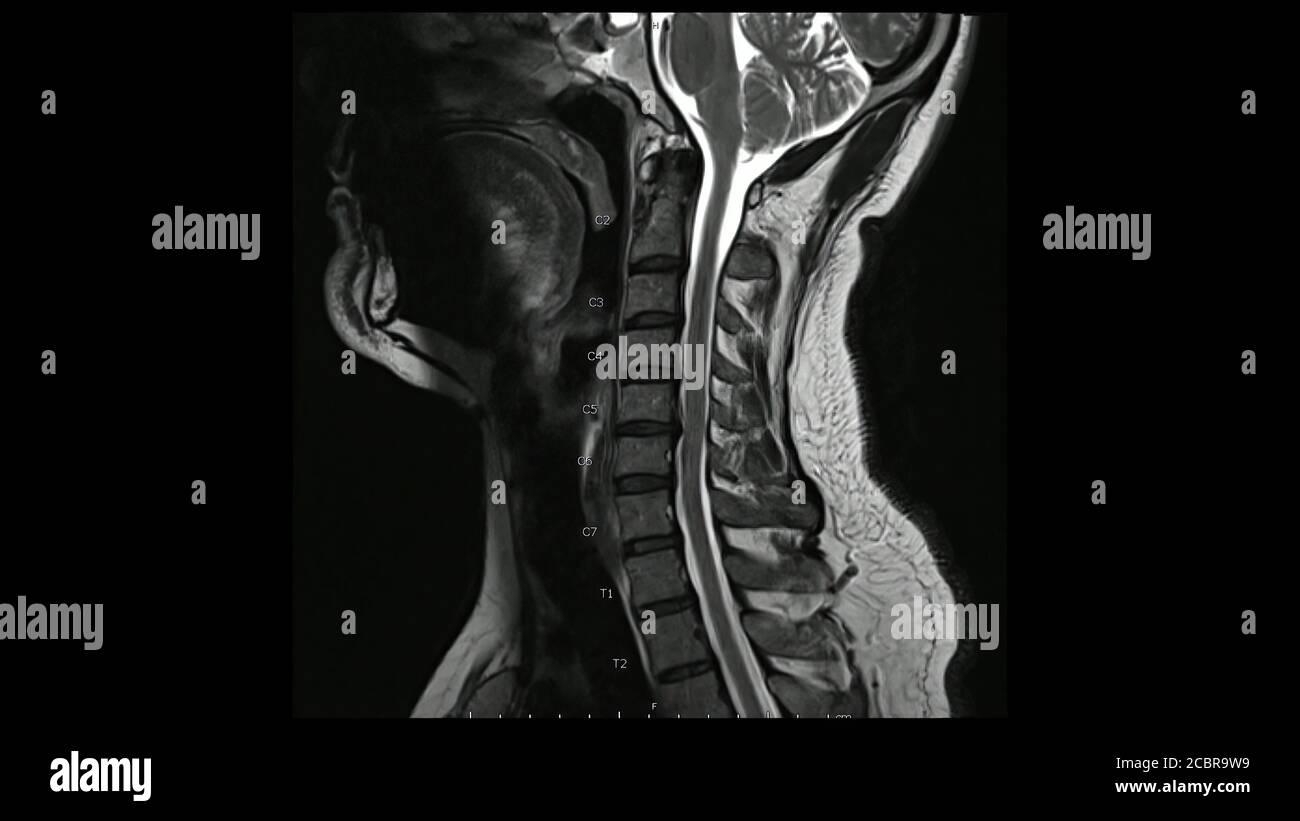

WebLa resonancia magnética de la columna cervical es un estudio preciso y seguro. Además, permite diagnosticar problemas neurológicos y esqueléticos. En. WebUna resonancia magnética de la columna cervical puede ayudar a evaluar varios síntomas y a diagnosticar tumores, hemorragias, infecciones o inflamaciones en las. WebLa resonancia magnética (o MRI) es un tipo de imaginería médica seguro y no invasivo que utiliza ondas de radio y un campo magnético para producir imágenes.

WebLa Rm de la columna cervical está indicada en pacientes con dolor cervical con o sin traumatismo, sospecha de hernia discal, la planificación de cirugía y posterior. WebA menudo, las pruebas no son necesarias porque la mayoría de los dolores cervicales están causados por espasmos musculares y esguinces, que el médico diagnostica. WebLa principal ventaja de las imágenes de resonancia magnética antes de los métodos de radiación es una visualización clara de las fibras nerviosas, que permite. WebLa región cervical consta de siete secciones, o de vértebras, etiquetado como el atlas, el eje, y C-3, C-4, C-5, C-6 y C-7. Básico de los conocimientos anatómicos, es. WebLa resonancia magnética también se conoce como resonancia magnética nuclear (RMN) y tomografía por resonancia magnética (MRT). Una resonancia magnética cervical con. WebLa Resonancia de Columna Cervical permite detectar una variedad de afecciones de la columna cervical y problemas en los tejidos blandos de la columna vertebral,.

Fotos Imagen por resonancia magnética de la columna cervical de un paciente